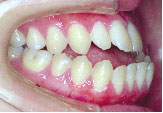

あごのずれもなくなり、バランスのとれた美しい口元になりました。咬み合わせも非常に良くなってご本人は大変満足されています。

治療期間は3年7か月です。